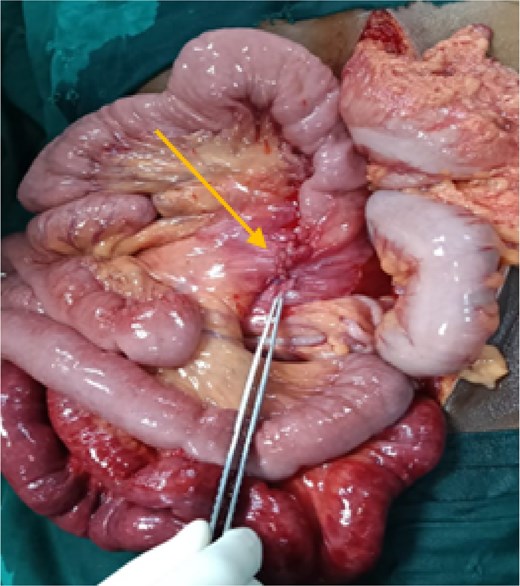

After initial resuscitation, the patient underwent emergency exploratory laparotomy. Intra-operatively, a large hernial sac was found near the third part of the duodenum behind ascending colon and right side of transverse colon containing gangrenous small bowel loops (Fig. 2). Lateral peritoneal attachments were divided and the caecum, ascending colon were mobilized medially representing the nonrotated gut. This manoeuvre exposed the underlying mesenteric defect. The hernial sac was opened widely which contained ileum and jejunum. After gentle reduction of the contents, the hernial opening was identified as a congenital defect adjacent to the third part of the duodenum, with the superior mesenteric vessels forming its medial boundary (Fig. 3). The margins of the defect within the mesocolon were carefully delineated and closed using absorbable 3-0 Vicryl in a continuous fashion (Fig. 4). Approximately 1 metre of gangrenous ileum, located 30 cm proximal to the ileocaecal junction, was resected. Given the patient’s hemodynamic instability and bowel condition, the proximal ileum was exteriorized as an end ileostomy in the left iliac fossa, and a distal mucus fistula was created in the right iliac fossa. The patient recovered well and was discharged on postoperative day 10.

Intraoperative picture showing hernial sac with defect following reduction of bowel loops.